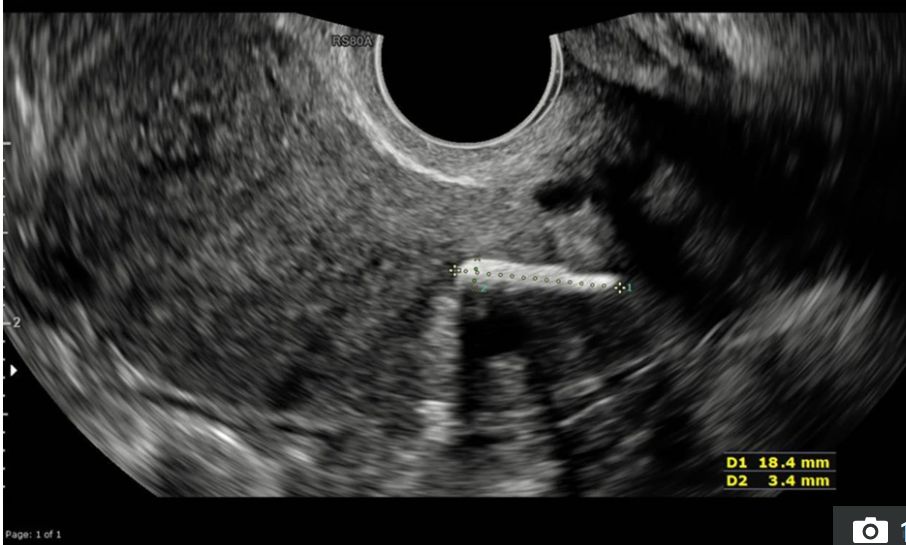

Mniej więcej rok później kobieta wróciła do kliniki ginekologicznej, skarżąc się na przewlekły ból w lewym boku i długie, bolesne okresy. Została zapisana na test barwnika, który miał sprawdzić, czy nie choruje na zespół policystycznych jajników (PCOS). W oczekiwaniu na operację pacjentka została poddana powtórnemu badaniu USG miednicy. Wtedy w tkance jej macicy odkryto ciało obce.

Ale dopiero podczas badania fizycznego i wykonania testu barwnika, okazało się, co jest przyczyną bólu i niemożności zajścia w ciążę. Lekarze wiedzieli, że kobieta przeszła aborcję chirurgiczną dwie dekady temu i doszli do wniosku, że ciałem obcym, które wykryto, jest kość płodu, która pozostała w łonie kobiety.

"Zatrzymanie kości płodu jest rzadkim, ale niedostatecznie zdiagnozowanym powikłaniem po aborcji. Nieleczona może powodować zaburzenia miesiączkowania i wtórną niepłodność" - napisano w raporcie.

Zauważono, że ani wcześniejszy rezonans magnetyczny oraz ultradźwięki nie wykryły kawałka kości, dlatego objawy kobiety były błędnie diagnozowane od lat.